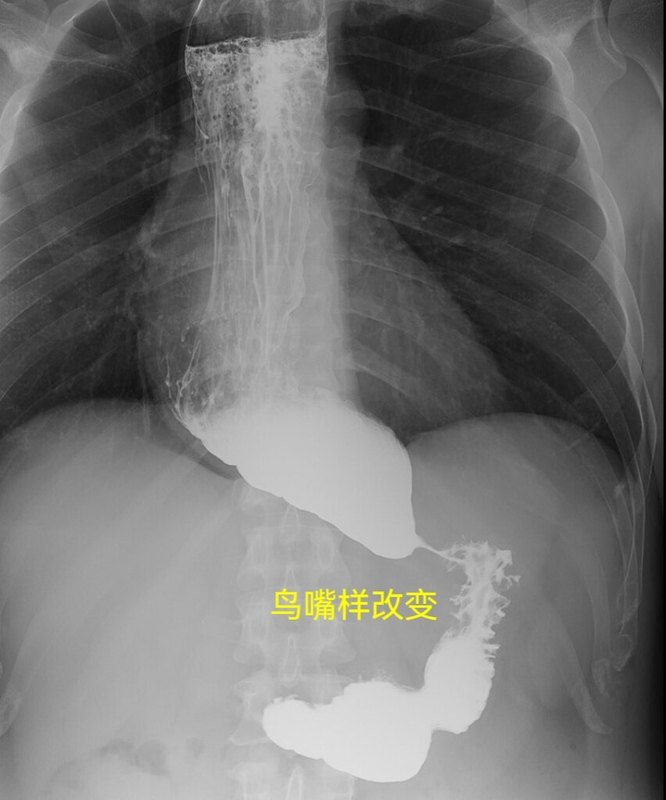

一、概念賁門失弛緩癥是一種以食管下括約肌松弛障礙,和食管體部無蠕動為主要特征的原發(fā)性食管動力紊亂性疾病,也被稱為巨食管癥或賁門痙攣。其主要特征是食管缺乏蠕動,食管下端括約?。↙ES)高壓和對吞咽動作的松弛反應(yīng)減弱。臨床表現(xiàn)為吞咽困難、胸骨后疼痛、食物反流以及因食物反流誤吸入氣管所致咳嗽、肺部感染等癥狀。二、病因和分型賁門失弛緩癥可分為原發(fā)性和繼發(fā)性,繼發(fā)性賁門失弛緩癥的病因常常是惡性腫瘤。原發(fā)性賁門失弛緩癥的病因迄今不明。一般認(rèn)為是神經(jīng)肌肉功能障礙所致。其發(fā)病與食管肌層內(nèi)乙酰膽堿神經(jīng)節(jié)細(xì)胞變性、減少或缺乏以及副交感神經(jīng)分布缺陷有關(guān)。有研究表明,賁門失弛緩癥肌間神經(jīng)叢的乙酰膽堿脂酶陽性神經(jīng)減少,伴LES乙酰膽堿脂酶活性減低,減低了乙酰膽堿的水解速度,導(dǎo)致堆積,升高了平滑肌的收縮力,導(dǎo)致發(fā)生賁門失弛緩癥。神經(jīng)節(jié)細(xì)胞退變的同時(shí),常伴有淋巴細(xì)胞浸潤的炎癥表現(xiàn),或許病因與感染、免疫因素有關(guān)。三、臨床表現(xiàn)早期可無任何癥狀。隨著病情進(jìn)展,可逐漸出現(xiàn)吞咽困難、食物反流、胸骨后疼痛不適、體重下降等癥狀。如發(fā)生反流物累及呼吸道,還可有咳嗽、咳痰、呼吸困難等呼吸系統(tǒng)癥狀。1、吞咽困難吞咽困難是最常見最早出現(xiàn)的癥狀。起病緩慢,多呈間歇性發(fā)作,常因情緒波動、進(jìn)食過冷過熱和辛辣刺激性食物而誘發(fā)。病初咽下困難,初期時(shí)有時(shí)無,時(shí)輕時(shí)重,后期則轉(zhuǎn)為持續(xù)性,進(jìn)食固體食物和液體食物均吞咽困難,少數(shù)甚至咽下液體較固體食物更困難。2、胸骨后疼痛可為悶痛、灼痛、針刺痛,疼痛部位多在胸骨后及中上腹,疼痛發(fā)作有時(shí)酷似心絞痛,甚至舌下含硝酸甘油片后可獲緩解。隨著吞咽困難的逐漸加劇,梗阻以上食管的進(jìn)一步擴(kuò)張,疼痛反而逐漸減輕。3、食物反流隨著吞咽困難的加重,食管的進(jìn)一步擴(kuò)張,相當(dāng)量的內(nèi)容物可潴留在食管內(nèi)至數(shù)小時(shí)或數(shù)日之久,而在體位改變時(shí)反流出來,在并發(fā)食管炎、食管潰瘍時(shí),反流物可含有血液。因?yàn)槭彻芘c氣道密切相連,食物反流后容易誤吸,導(dǎo)致出現(xiàn)咳嗽、咳痰,發(fā)生呼吸道感染或吸入性肺炎。4、體重下降癥狀比較嚴(yán)重或者病程比較長的患者,會因?yàn)殚L期進(jìn)食困難,導(dǎo)致體重下降、營養(yǎng)不良、貧血和維生素缺乏等表現(xiàn)。四、輔助檢查1、食管鋇劑(碘劑)X線造影:是首選的診斷方法食道造影檢查見食管擴(kuò)張,食管蠕動減弱,食管末端狹窄呈鳥嘴狀,狹窄部黏膜光滑,是賁門失馳緩癥患者的典型表現(xiàn)。Henderson等將食管擴(kuò)張分為三級:I級(輕度),食管直徑小于4cm;II級(中度),食管直徑4~6cm;III級(重度),食管直徑大于6cm,甚至彎曲呈S形。2、胃鏡檢查:可排除器質(zhì)性狹窄或腫瘤內(nèi)鏡下賁門失弛緩癥表現(xiàn)特點(diǎn):?1)食管內(nèi)殘留有中到大量的積食,多呈半流質(zhì)狀態(tài)覆蓋管壁,且黏膜水腫增厚致使失去正常食管黏膜色澤;2)食管體部擴(kuò)張,并有不同程度扭曲變形;3)管壁可呈節(jié)段性收縮環(huán),似憩室膨出;4)賁門狹窄程度不等,直至完全閉鎖不能通過。需要注意的是有時(shí)鏡身通過賁門感知阻力不甚明顯時(shí)易忽視該病。3、食管動力學(xué)檢測根據(jù)HRM,賁門失弛緩癥可分為三個臨床亞型(芝加哥分型):①?Ⅰ型(經(jīng)典型):食管體部無明顯增壓;100%吞咽為無蠕動;IRP>正常值(取決于導(dǎo)管)。②?Ⅱ型(食管增壓型):≥20%的吞咽出現(xiàn)因同步收縮引起的食管增壓,正常蠕動消失;IRP>正常值(取決于導(dǎo)管)。③?Ⅲ型(痙攣型):≥20%的吞咽為期前收縮,并且DCI>450,正常蠕動消失;IRP>正常值(取決于導(dǎo)管)。芝加哥分型也可用來療效預(yù)測:Ⅱ型對治療有效率高,Ⅰ型次之,而Ⅲ型效果最差。五、診斷1、典型臨床表現(xiàn):間歇性吞咽困難,部分患者進(jìn)食液體食物比固體食物困難,有胸骨后疼痛、食物反流、體重下降等。2、鋇餐檢查:食管末端狹窄呈鳥嘴狀,食管擴(kuò)張,食管蠕動減弱。3、胃鏡檢查:除外器質(zhì)性狹窄或腫瘤。4、食管動力學(xué)檢測:用于分型。六、鑒別診斷1、心絞痛多由勞累誘發(fā),含服硝酸甘油有效。而賁門失弛緩癥則為吞咽所誘發(fā),并有咽下困難。2、食管神經(jīng)官能癥(如癔球癥)大多表現(xiàn)為咽至食管部位有異物阻塞感,但進(jìn)食并無梗噎癥狀。3、食管癌、賁門癌癌性食管狹窄的X線特征為局部黏膜破壞和紊亂,做胃鏡取病理可見癌細(xì)胞。4、繼發(fā)性賁門失弛緩癥繼發(fā)性賁門失弛緩癥是指由胃癌、食管癌、肺癌、肝癌、胰腺癌、淋巴瘤等惡性腫瘤、淀粉樣變、結(jié)節(jié)病、神經(jīng)纖維瘤病、嗜酸細(xì)胞性胃腸炎、慢性特發(fā)性假性腸梗阻等所引起的類似原發(fā)性賁門失弛緩癥的食管運(yùn)動異常。七、并發(fā)癥1、吸入性呼吸道感染食管反流物被吸入氣道時(shí)可引起支氣管和肺部感染,尤其在熟睡時(shí)更易發(fā)生。約1/3患者可出現(xiàn)夜間陣發(fā)性嗆咳或反復(fù)呼吸道感染。2、食管本身的并發(fā)癥可繼發(fā)食管炎、食管黏膜糜爛、潰瘍和出血、食管-氣管瘺、自發(fā)性食管破裂和食管癌等。八、治療1、一般治療盡量避免吃不好消化的固體食物,多進(jìn)食流質(zhì)或半流質(zhì)食物,少吃多餐,細(xì)嚼慢咽。2、藥物治療服用鎮(zhèn)靜解痙藥物,如口服1%普魯卡因溶液。硝酸酯類(硝酸甘油)及鈣通道阻滯劑(硝苯地平、硝苯吡啶)等藥物可減少食管下括約肌的壓力,使患者吞咽困難及疼痛的癥狀減輕。但并不是對所有人都能夠起效,而且僅用于臨時(shí)緩解癥狀,長期(1年后)療效差。3、內(nèi)鏡治療經(jīng)口內(nèi)鏡下肌切開術(shù)(POEM)治療賁門失馳緩癥取得了良好的效果。手術(shù)無皮膚切口,通過內(nèi)鏡下賁門環(huán)形肌層切開,最大限度地恢復(fù)食管的生理功能并減少手術(shù)的并發(fā)癥,術(shù)后早期即可進(jìn)食,術(shù)后約95%的患者吞咽困難得到緩解,且反流性食管炎發(fā)生率低。由于POEM手術(shù)時(shí)間短,創(chuàng)傷小,恢復(fù)特別快,療效可靠,是目前治療賁門失弛緩癥的最佳選擇。4、手術(shù)治療對中、重度及傳統(tǒng)內(nèi)鏡下治療效果不佳的病人應(yīng)行手術(shù)治療。賁門肌層切開術(shù)(Heller手術(shù))是目前最常用的術(shù)式??山?jīng)胸或經(jīng)腹手術(shù),也可在胸腔鏡或者腹腔鏡下完成。遠(yuǎn)期并發(fā)癥主要是反流性食管炎,因而有人主張附加抗反流手術(shù),如胃底包繞食管末端360度(Nissen手術(shù))、270度(Belsey手術(shù))、180度(Hill手術(shù))或?qū)⑽傅卓p合在食管腹段和前壁(Dor手術(shù))。

各種考試??荚囶}目:上消化道造影呈鳥嘴樣改變的疾病,它來了![呲牙]?男性,40歲,進(jìn)食梗阻伴夜間食物反流2年余?上消化道造影檢查提示食管擴(kuò)張,賁門鳥嘴樣狹窄。胸部CT提示食管明顯擴(kuò)張伴內(nèi)容物,食管胃連接處狹窄。?節(jié)前入院,禁食、完全胃腸外營養(yǎng)、食管減壓沖洗后食管擴(kuò)張明顯改善今日行腹腔鏡下(5孔法)Heller肌層切開+賁門Dor成形術(shù)。

賁門失弛緩癥——反流之下的隱藏者